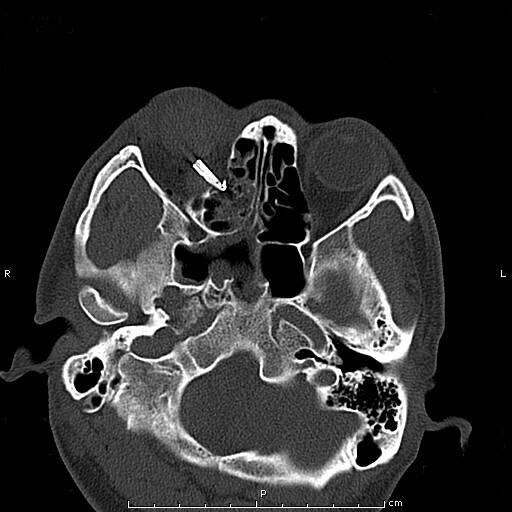

患者青年男性,因“右眼被钢笔戳伤2小时余”入院,眼科查体:视力:右无光感,左0.4。眼压:右不能检查,左正常。右眼上睑红肿,钢笔自颞上方眼睑刺入,末端位置不详,睁眼困难;结膜充血、水肿,角膜尚清,前房积血,余眼内结构窥不入。左眼未见明显异常。入院后完善眼眶CT检查,印象:右眼眶异物并右眼球破裂伤、眶内壁骨折,异物嵌顿于眶壁。钢笔内含墨水,伤情重且复杂。

经科室讨论、充分评估患者病情,与患者进行病情沟通后,拟于全麻下实施右眼眶壁异物取出+眼球破裂伤清创缝合探查+眼睑皮肤裂伤清创缝合+万古霉素玻璃体腔注药术。由于钢笔笔尖与笔筒游离且笔尖弯曲倒钩于眶壁,使异物取出难度大大增加,经专家团队讨论,决定在鼻内窥镜协助下联合眶内入路分离、截断内直肌、下直肌成功将眶内壁异物自鼻腔完整取出,手术取得圆满成功。